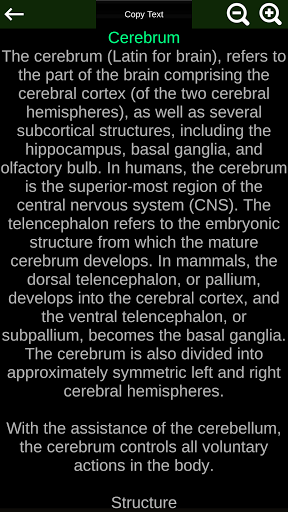

Internal Organs in 3D Anatomy لـ Vodafone Smart N9 Lite

(الأجهزة الداخلية في)

Internal Organs 3D Anatomy 3.4